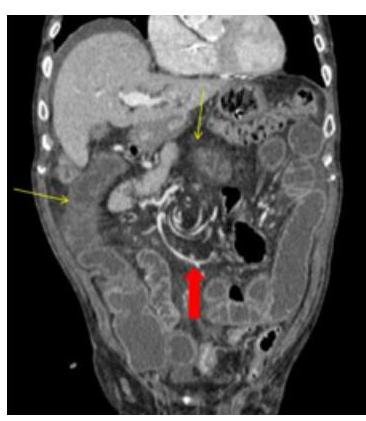

Contenido mejorado por IA (Markdown)

# VÓLVULO DE COLON ## DEFINICIÓN Un **vólvulo** se define como la torsión de un órgano a través de un eje, sobre su pedículo vascular. El vólvulo de colon típicamente resulta en una obstrucción intestinal en asa cerrada. La rotación del pedículo vascular y la dilatación del colon contribuye a compromiso de la perfusión del colon.  ## LOCALIZACIÓN 1. **SIGMOIDES** (la más frecuente) 2. Ciego (frecuente en mujeres de edad media)  # EPIDEMIOLOGÍA - Corresponde a 1 - 7 % de todas las oclusiones intestinales - Tasa de mortalidad 7 - 20 % - Es más común en América Latina, África y Europa del Este - En naciones de primer mundo es relativamente raro. - En esos países es la 3a causa de obstrucción de colon (después de neoplasias y enfermedad diverticular) ## FACTORES DE RIESGO CIEGO - Femeninos de edad media. - Cirugías abdominales previas - Adultos mayores con inactividad prolongada ## FACTORES DE RIESGO SIGMOIDES - Masculinos - Edad mayor 60 años - Pacientes adultos mayores institucionalizados - Estreñimiento crónico - Enfermedad neuropsiquiátrica - Retraso mental - Desórdenes neurológicos - Cirugías abdominales previas - Embarazo (**causa más frecuente de obstrucción**) - Infestación por gusanos redondos - Megacolon (Chagas y Hirschprung) ## CLINICA ## CUADRO DE OBSTRUCCIÓN INTESTINAL QUE CURSA CON DOLOR ABDOMINAL Y DISTENSIÓN (ASA CERRADA) ## - DOLOR ABDOMINAL - Distensión abdominal **SÚBITA Y ESPECTACULAR**. - Ausencia de canalización de gases - Ausencia de evacuaciones - Náusea y vómito - Hipersensibilidad abdominal - Resistencia muscular - Ruidos peristálticos de tono metálico - Fosa ilíaca izquierda vacía a la palpación abdominal **ISQUEMIA / PERFORACIÓN** Dolor Intenso + Irritación Peritoneal + Datos de Sepsis. - Ausencia de materia fecal en exploración rectal - Materia fecal melénica en el recto (poco común) # DIAGNÓSTICO Laboratorio: realizar BH, QS, ES y pruebas de coagulación en todos los sospechosos de Vólvulo. ## ESTUDIOS DE IMAGEN. ## RADIOGRAFÍA ABDOMEN - Permite diagnóstico en mayor porcentaje en los Sigmoides que en los Cecales - Solicitar de pie (buscando aire libre subdiafragmático = Perforación) y decúbito. - Realizarla en ausencia de TAC de urgencias ## Hallazgos Cecales: 1. Asa desproporcionadamente dilata y patrón de oclusión distal (91%) 2. Nivel hidroaéreo único en el ciego y colapso de colon distal (82%)  ## ENEMA DE BARIO - Es más útil en el sigmoides que en el cecal - Contraindicada en sospecha de peritonitis. - Realizarlo en sospecha de Vólvulo sigmoides cuya radiografía no sea concluyente o TAC no accesible. - Imagen en "pico de ave" o "as de espadas" en el punto del vólvulo sigmoides, producida por el medio de contraste en el enema de bario.  ## TOMOGRAFÍA COMPUTARIZADA Es el **ESTUDIO CON MAYOR PROBABILIDAD DIAGNÓSTICA** tanto en Sigmoides (89%) y Ciego (71.4%). ## Hallazgos Sigmoides - Signo del Grano de café + Nivel hidroaéreo único + Colapso de Colon Izquierdo - Signo del remolino (flecha roja) - - Distensión del ciego de +10 cm  # TRATAMIENTO SIGMOIDES ## MANEJO MÉDICO 1. REANIMACIÓN TEMPRANA: - Balance adecuado de líquidos y electrolitos - Apoyo ventilatorio (en caso necesario) - Descompresión Intestinal con **SONDA NASOGÁSTRICA** 2. ANTIBIÓTICOS: deben ser **amplio espectro** con cobertura anaeróbica en pacientes con peritonitis, isquemia o sepsis. 3. MONITORIZACIÓN URINARIA: si es necesario **SONDA URINARIA TRANSURETRAL** para adecuado control de líquidos. ## RESOLUCIÓN NO QUIRÚRGICA Posterior al diagnóstico de Vólvulo y dependiendo las condiciones del paciente, se puede realizar la destorsión y descompresión del vólvulo sin cirugía: ## 1ra elección: SIGMOIDOSCOPÍA O COLONOSCOPÍA DE EMERGENCIA. 1. El recto se insulfa para proporcionar buena visibilidad y facilitar el ápice del vólvulo. 2. Si la distorsión no ocurre, se introduce un tubo rectal suave dirigido bajo visión directa. 3. La punta del endoscopio puede ser utilizada con constante presión en el ápice del vólvulo. - Tasa de éxito de destorsión no quirúrgica 96 - 64 % (más exitosa en sigmoidoscopía rígida en comparación a colonoscopía. Recurrencia de 43 % en 32 días y 85 % en los siguientes 8 meses. ## POSTERIOR A LA REDUCCIÓN DEL VÓLVULO - PROGRAMAR Qx DEFINITIVA ELECTIVA. ## RESOLUCIÓN QUIRÚRGICA ## RESECCIÓN DE SIGMOIDES CON ANASTOMOSIS PRIMARIA ## CIRUGÍA ELECTIVA - Indicada de forma electiva o semielectiva a los pacientes con resolución no quirúrgica del vólvulo. - Se sugiere hacerla durante el mismo periodo de hospitalización. ## CIRUGÍA DE URGENCIA - Pacientes con vólvulo con evidencia de **PERITONITIS, ISQUEMIA O NECROSIS** o cuando el tratamiento no quirúrgico no resulta exitoso. - COLECTOMÍA TOTAL - indicada en megacolon o megarrecto asociado a vólvulo sigmoides. # TRATAMIENTO CIEGO ## 1ra elección: MANEJO QUIRÚRGICO. - Valorar edad, condición, presencia de comorbilidad grave y el estado de la pared del ciego. - Examinar el colon distal en el transoperatorio en búsqueda de una oclusión distal como posible causa. RESECCIÓN DEL VÓLVULO CECAL + HEMICOLECTOMÍA DERECHA + ANASTOMOSIS PRIMARIA - Alternativa: Ileostomía + Fístula mucosa distal DESTORSIÓN + CECOPEXIA - Indicada en pacientes con alto riesgo de morbimortalidad para resección segmentaria # ALGORTIMO MANEJO DEL VÓLVULO